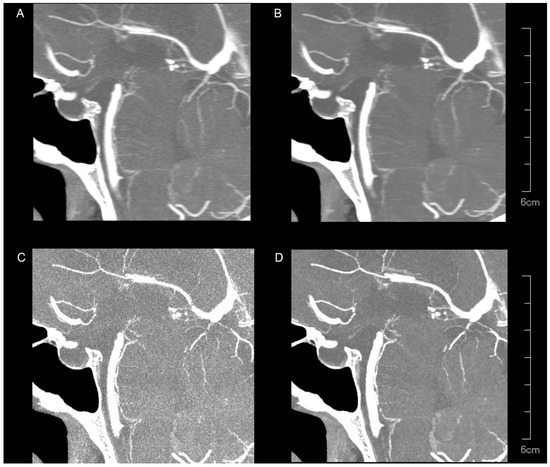

| Kernel Hv40 Without QIR | Kernel Hv40 with QIR | Kernel Hv72 Without QIR | Kernel Hv72 with QIR | p | |

|---|---|---|---|---|---|

| LSA region | |||||

| SNR | 78.0 (55.5–105.0) | 76.6 (50.3–115.9) | 55.7 (34.1–75.8) | 85.4 (54.9–121.8) | <0.00001 |

| CNR | 10.6 (5.9–16.8) | 10.3 (4.9–26.2) | 4.3 (2.6–6.4) | 11.3 (6.4–17.6) | <0.00001 |

| PA region | |||||

| SNR | 74.1 (44.6–126.4) | 83.2 (41.5–161.1) | 60.7 (40.0–80.8) | 101.0 (46.5–145.9) | <0.00001 |

| CNR | 9.9 (4.1–19.8) | 12.8 (3.5–32.8) | 5.0 (3.1–6.8) | 13.6 (3.9–19.9) | <0.00001 |